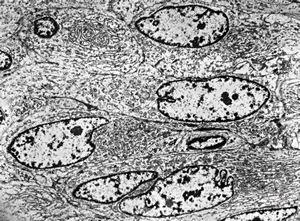

F,32y. | transversally sectioned skeletal muscle cell

mouse skeletal muscle cell - transversal section